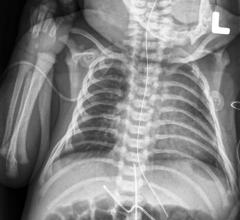

Agfa HealthCare announced the launch of Musica for Neonatal, built on its next generation Musica image processing software. Offering dedicated functions for neonatal imaging, the next generation Musica for Neonatal can play an important role in caregivers' efforts to control and reduce imaging radiation dose in these highly sensitive patients, while offering very high image quality and consistency.

Meridian Medical Systems announced it has received U.S. Food and Drug Administration (FDA) clearance to market its Meridian Monarch ultra high definition (UHD) Universal Digital Imager (UDI) with wireless detector and automatic exposure detection (AED). The approval process included the Monarch UDI 2 and the Monarch UDI 2 with wireless/AED. The digital system has been cleared to be used for both pediatric and adult radiographic imaging.